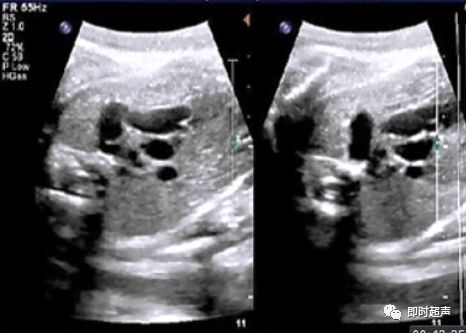

侧动探头连续观察即可观察到动脉导管走形迂曲,但还是汇入降主动脉

动脉导管瘤

胎儿动脉导管瘤的预后

- 动脉导管迂曲扩张和动脉导管瘤对新生儿最常见的影响就是动脉导管未闭。但随着研究的深入,发现动脉导管未闭的发生率并不是很高。

- 但有文献报道,少数动脉导管瘤会发生严重的并发症,甚至导致新生儿死亡。因此,如在产前发现动脉导管瘤或迂曲扩张,应提示临床并追踪。

晚孕期胎儿右心扩大的鉴别诊断

- 晚孕期常可观察到胎儿右心比左心大,这常常会造成检查医生的担忧。

- 一般而言,晚孕期胎儿右心就会比左心稍大,这主要是由于胎儿肺循环阻力升高的原因,所以只是右心稍大,大可不必紧张。

- 但如果是右心明显比左心大,那我们就要仔细甄别

- 晚孕期导致胎儿右心扩大的疾病有:妊娠糖尿病、胎儿心脏畸形、胎儿心肌疾病(心肌致密化不全,心内膜弹力纤维增生症)等。

- 如果没有其它病因而仅仅是动脉导管瘤或妊娠糖尿病的话,那么胎儿预后基本良好。

- 如果有胎儿畸形则需明确是何种畸形,再判断预后。